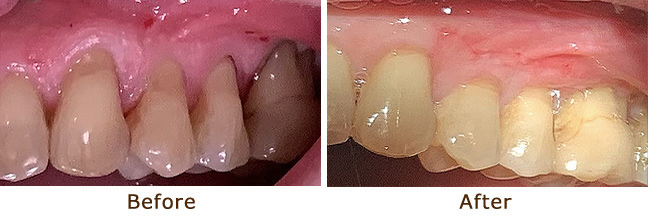

Gum Graft for Gingival Recession

Gum Graft for Gingival Recession